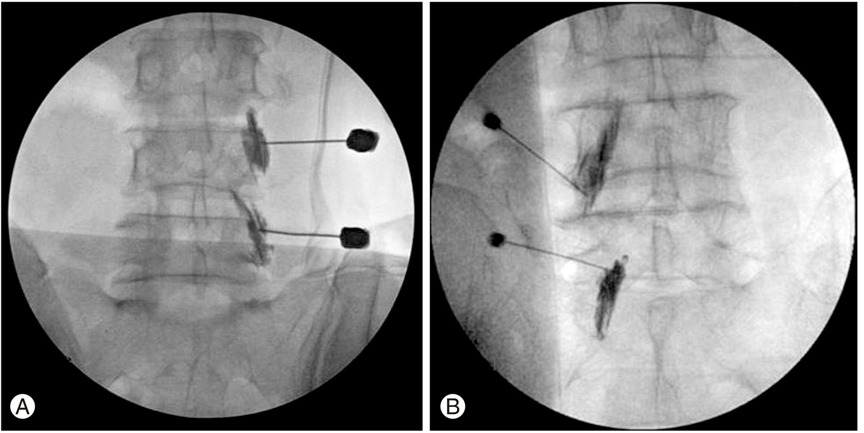

asj-6-163-g004-l.jpg 주사를 통하여 신경을 안정시키고 통증을 차단하는 약물을 주입.

사진은 주사바늘을 통해서 디스크에 의해 압박된 신경근을 찾아서 주사약을 투입하는 장면이다. 염색약을 통하여 신경근의 위치를 확인하고 안전하게 약물을 주사한다. 주사 시간은 보통 2~3분 내외이고 증상 호전은 즉각적으로 나타나는 경우가 많다.